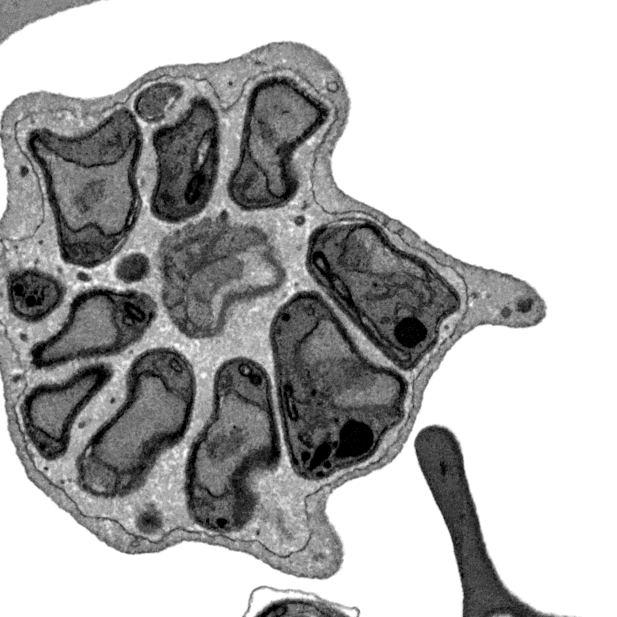

Actual z-index: 95Sampling: sampled from 190 source slicesScale: 10 x 10 x 20 nmContrast: per slice auto. Each generated plane is normalized independently for visual inspection.Frame cache: warming 0/96Keyboard: ←/→ step, Home/End jump.